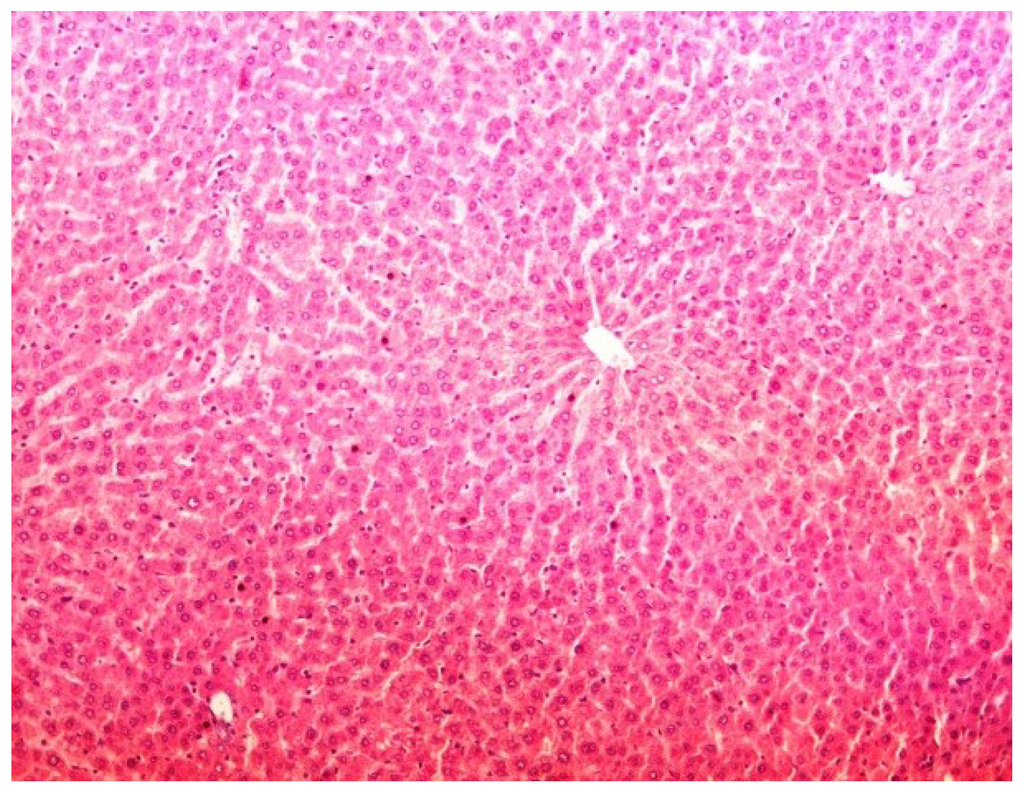

The histopathology of CCl4-induced rats when compared to normal hepatic architecture (Figure 2) showed massive fatty changes, necrosis, ballooning degeneration and the loss of cellular boundaries (Figure 3). The liver sections of plumieride at the dose level of 5 mg/kg body weight plus CCl4-treated rats (Group III) showed mild prevention of CCl4-induced degenerative changes with the few pyknotic nuclei and fatty vacuolizations in the cytoplasm (Figure 4). The liver sections of plumieride treated rats at the dose level of 10 mg/kg body weight along with CCl4 (Group IV) indicated partial amelioration of degenerative effects in hepatocytes but still show cloudy swelling and mild fatty changes (Figure 5). The histomorphological picture of liver sections of plumieride at the dose level of 20 mg/kg body weight along with CCl4-induction to rats (Group V) showed more or less normal labular patterns devoid of degenerative changes, and cytoplasm was preserved with prominent nucleus without intracellular lipid accumulation (Figure 6) almost comparable to the normal control and silymarin treated Group VI (Figure 7).

Figure 6.

Photomicrograph of rat liver section of CCl4 + Plumieride (20 mg/kg body weight), showing moderately brought central vein, hepatic cells with preserved cytoplasm and prominent nucleus at H & E × 100.